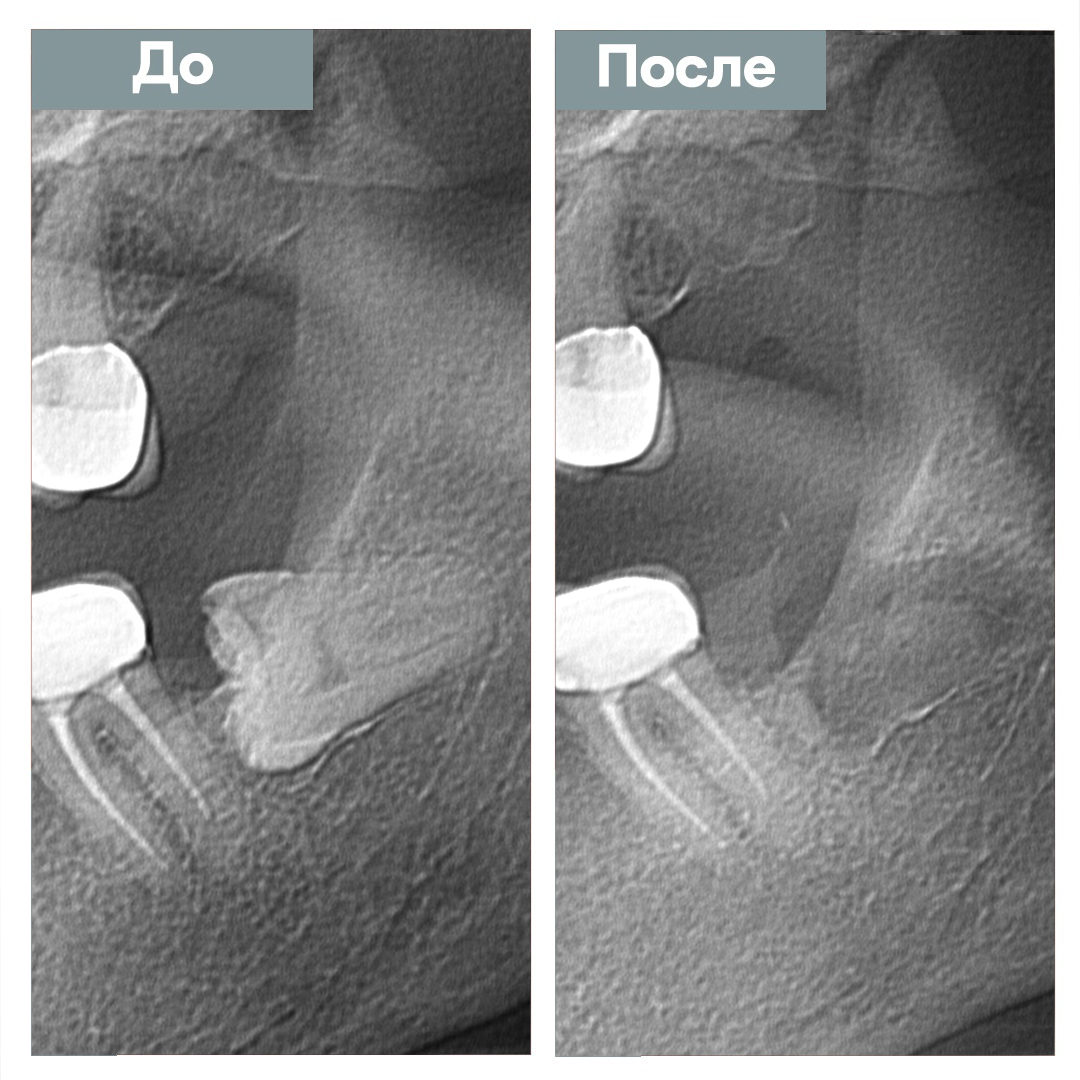

Удаление ретинированного зуба